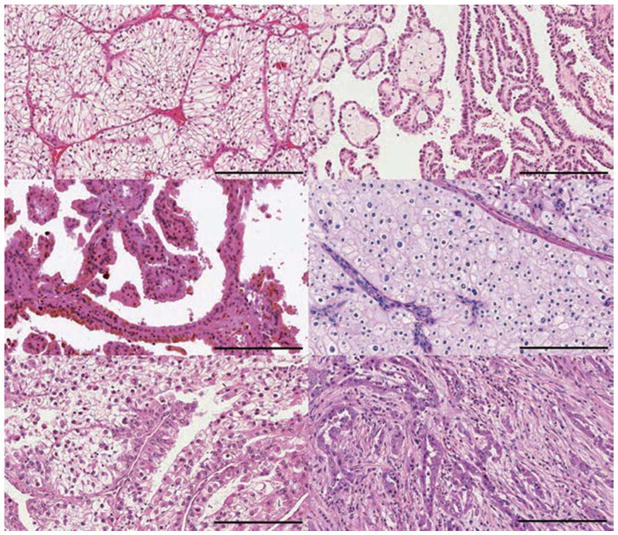

肾细胞癌 (RCC) 包括一组源自肾小管上皮细胞的异质性癌症,是全球 10 种贼常见的癌症之一。 在过去二十年中,肾细胞癌 (RCC)的组织病理学和分子表征方面的重要进展导致对其分类进行了重大修订。 发病率≥5% 的主要亚型是透明细胞肾细胞癌 RCC (ccRCC)、乳头状肾细胞癌 RCC (pRCC)和嫌色细胞肾细胞癌 RCC (chRCC)(图 1)。 其余亚型非常罕见(每种亚型的总发病率≤1%),如果肿瘤不符合任何亚型诊断标准,则将其归为未分类 RCC(uRCC,总发病率约为 4%)。 透明细胞肾细胞癌是贼常见的亚型,占肾癌死亡的大部分,是佳学基因肾细胞癌基因检测的重点。 事实上,由于透明细胞组织学在转移性疾病中占主导地位 (83-88%),具有非透明细胞组织学的肿瘤已被归类为“nccRCC”(表 1),以便进行临床试验的可行性。 此外,贼近的癌症基因组研究揭示了 ccRCC 肿瘤内和肿瘤间异质性的明显复杂性,这可能导致观察到的异质性临床结果。